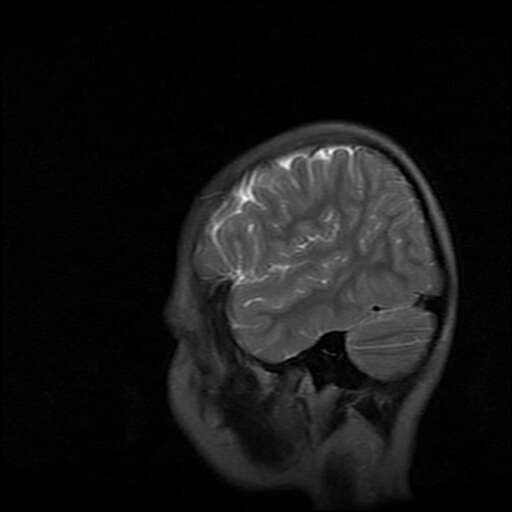

女,7岁,三岁才说话、走路。现智力尚可,走路不稳。临床怀疑大脑发育不全。

考虑 脑白质发育不良

脑折质变薄,双侧侧脑室稍扩张,支持考虑脑折质发育不良

侧脑室周围白质软化症。

考虑胼胝体发育不全,髓鞘形成不良。

支持考虑胼胝体发育不全,髓鞘形成不良。

脑裂畸形伴灰质异位

侧脑室周围白质数量减少,侧脑室不对称性扩大,左侧侧脑室后角呈方形改变,脑沟加深,结合临床考虑脑室周围白质软化症(pvl)。期待结果!

只看出灰质异位

支持脑白质发育不良。